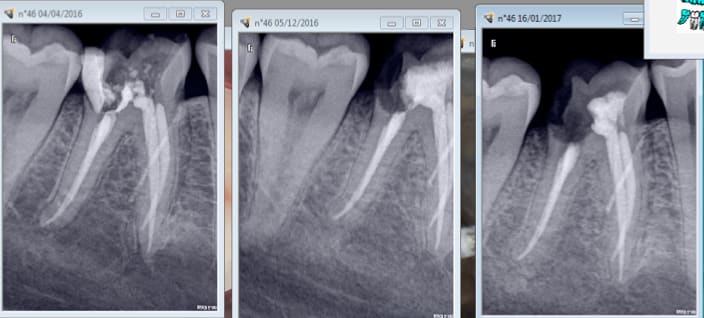

Tiens casa quand tu soignes la dent causale tu ne les revois plus........ non plus.

Enfin des fois si. 2006........2017. Et pas pour une visite de controle. -) -)

Je pense qu'il y a une image apicale sur 16 car je n'avais pas traité le MV2 à l'époque. Heureusement que je n'ai pas fait de couronne hein ? -) -))))

C'est la 15 qui a motivé la consult. Bizarre. -))))

Je vais commencer par 27....... une fois le devis signé ! -)))))))

Ah oui radios 8 secteurs. -))))

AH ! oui il a tardé en plus ( endo en avril 2016) ca n'arrange pas les choses-)))

PS: putain , j'avais pas vu les radio ,ç est bo que ç en devient enervant :-)